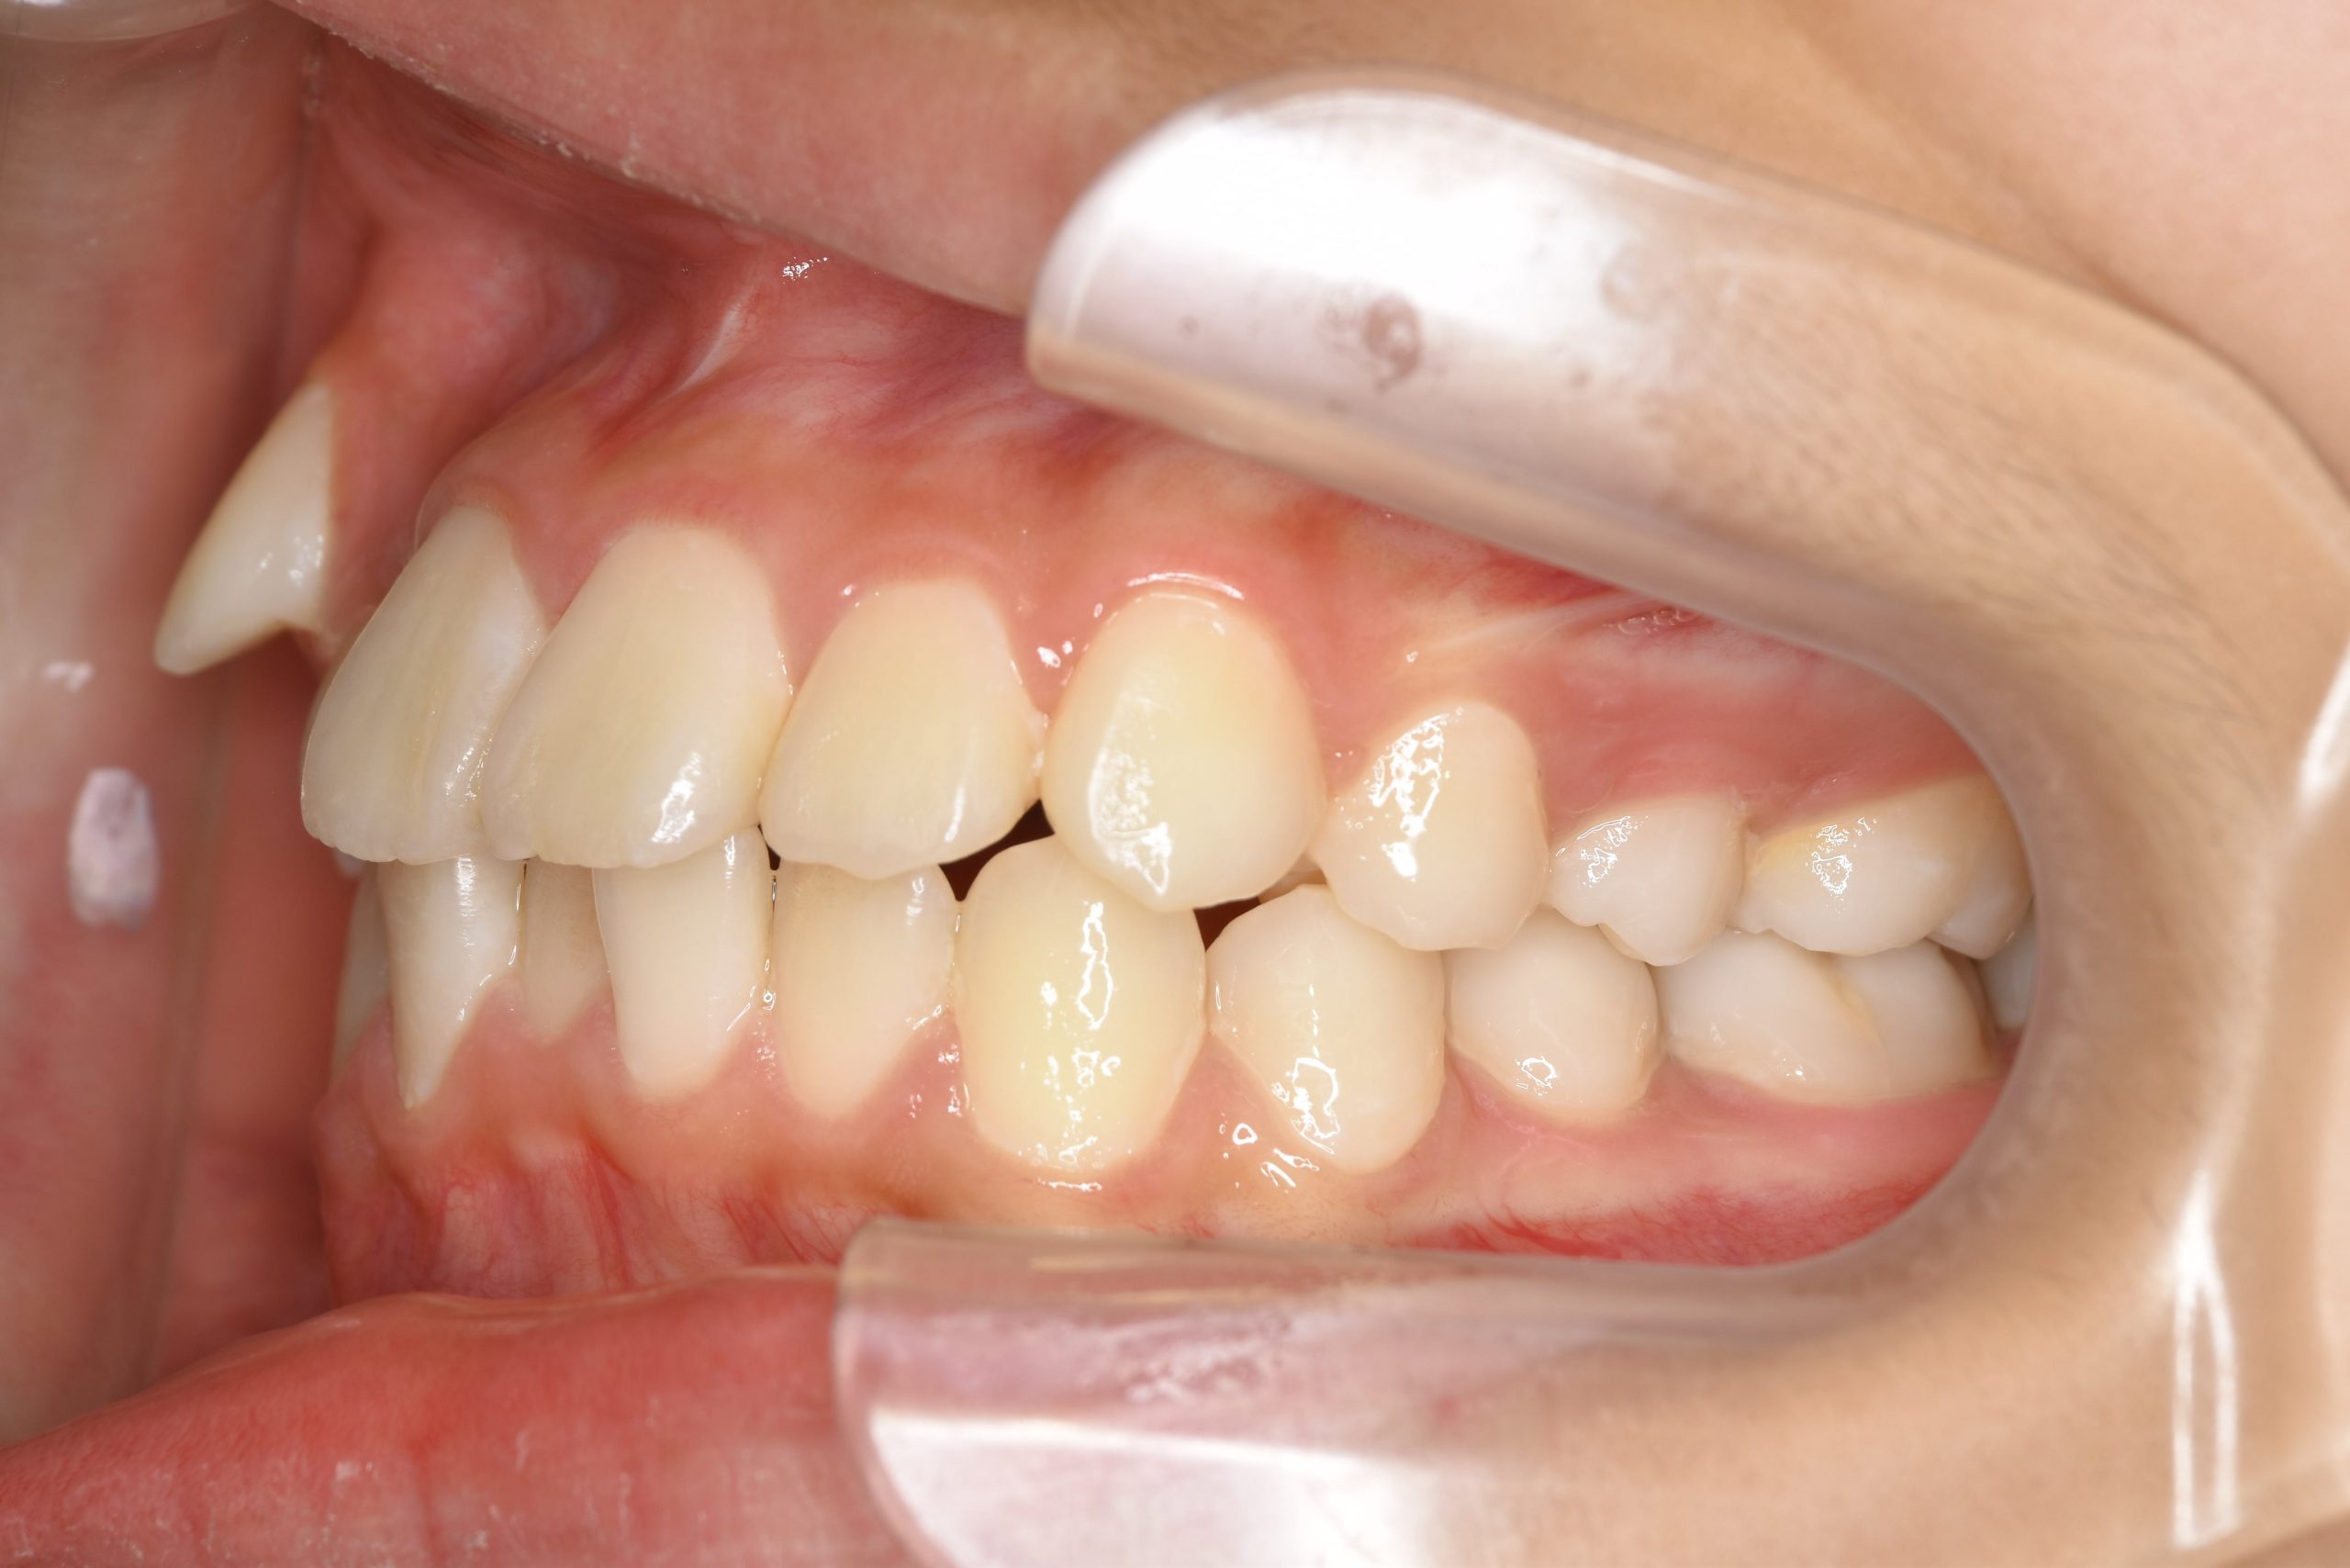

ビフォー

ワイヤー矯正治療|症例_1324

主訴 下顎が出ている

施術内容 MSEと下顎リンガルアーチを用いて上下顎骨を拡大した。

その後マルチブラケット装置を用いて非抜歯で歯牙を配列し、良好な咬合を獲得した。